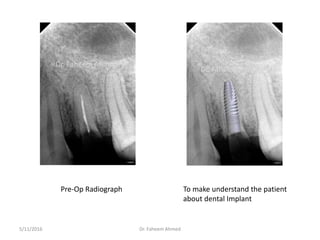

A 38-year-old male patient visited the clinic needing a tooth extracted from the upper left back tooth region. Upon examination, it was found to have a root canal treated root stump. The patient agreed to have the root extracted and immediately receive a dental implant. The root was carefully extracted to preserve the bone. A osteotomy was performed and a 4.2x14mm implant was placed, achieving an adequate torque of 40 Nm. Bone graft material was placed and sutures were used to complete the immediate implant procedure.